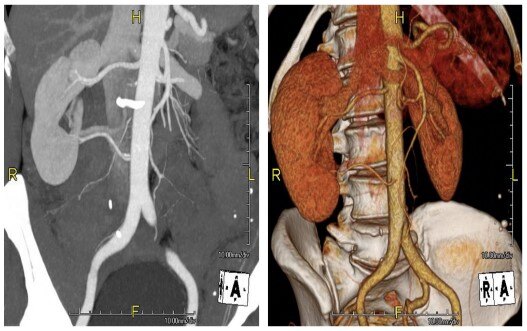

新型影像学和计算机辅助三维重建下的解剖结构细化:可以更好的减少缺血时间,尽早开放阻断的血管,间歇性阻断血管,超选阻断和无阻断血管。

新型节段性肾脏解剖: 精准描述肿瘤分割部位,大小和血供;计算机辅助PVA模型: 依据术前影像计算剩余实质体积,评估术后发生慢性肾功能不全的概率

从患者血管因素、肿瘤因素以及患者自身条件出发,选取最优手术入路 (开放、传统腹腔镜或达芬奇机器人辅助手术),做到“三精准原则”——精准阻断、精准切除,精准缝合。